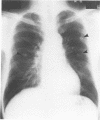

A case of axillary sweat gland carcinoma which metastasised to both lungs six years after resection of the primary lesion is described. The lesions were resected and three years later two further pulmonary metastases were resected.